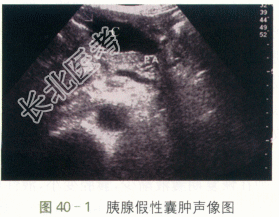

患者,女性,58岁,因“反复上腹部隐痛1月”就诊,伴恶心呕吐。无腹胀、腹泻,不伴皮肤、尿色改变。两月前有急性胰腺炎病史。

ALT341U/L,AST281U/L,AMS6111U/L。

二、影像资料

- 简答题4、胰腺假性囊肿的典型声像图特征有哪些?